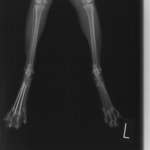

症例3:キルシュナーワイヤーのピンニングによる整復

ペルシャ猫 11ヶ月齢 雄

他院にて左大腿骨遠位の成長板骨折(salter-harrisⅠ型)が認められており、治療相談を目的として来院。当院にて、キルシュナーワイヤーを用いたピンニングにより骨折部位の整復を行いました。術後の経過は良好で、現在も経過観察中です。

術前レントゲン

術後レントゲン